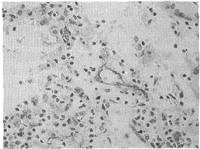

2.1 不同肺组织中MVD的比较 肺癌组织中MVD为30.47±10.56,肺良性病变肺组织中MVD为10.23±6.92。肺癌组织中MVD显著高于肺良性病变肺组织(P<0.01)(图1、2)。

图 1 肺良性病变组织中血管内皮细胞表达

阳性细胞浆呈棕黄色(FⅧ-Ab,1∶100,LSAB法×175)

Fig 1 FⅧ-factor expression of vascular endothelial cell in benign pulmonary tissue. Positive cell cytoplasm showed brown-yellow(FⅧ-Ab,1∶100,LSAB method×175)

图 2 肺癌组织中血管内皮细胞表达

阳性细胞浆呈棕黄色(FⅧ-Ab,1∶100,LSAB法×350)

Fig 2 FⅧ-factor expression of vascular endothelial cell in lung cancer tissue. Positive cell cytoplasm showed brown-yellow(FⅧ-Ab,1∶100,LSAB method×350)